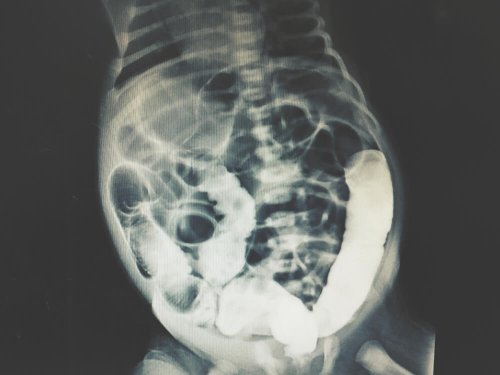

Oggi il lavaggio peritoneale diagnostico è un esame medico altamente affidabile, dato che i risultati sono raramente dei falsi positivi o errori di altro genere. Inoltre, viene eseguito insieme ad altri esami di diagnostica per immagini, quali la TAC (Tomografia Assiale Computerizzata) o la RM (Risonanza magnetica).

Sulla base dei risultati ottenuti, l’equipe medica determinerà la causa dell’anomalia addominale. Inoltre, possono essere eseguiti esami finalizzati all’ottenimento di immagini interne della regione addominale, in modo da facilitare la diagnosi.